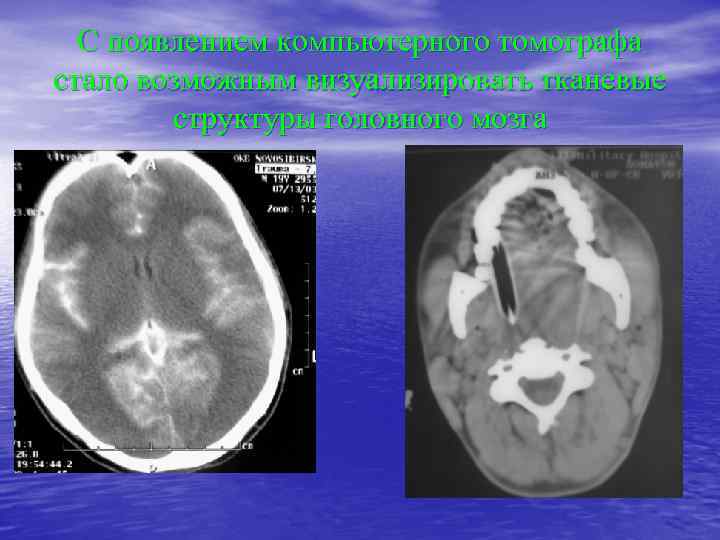

С появлением компьютерного томографа стало возможным визуализировать тканевые структуры головного мозга